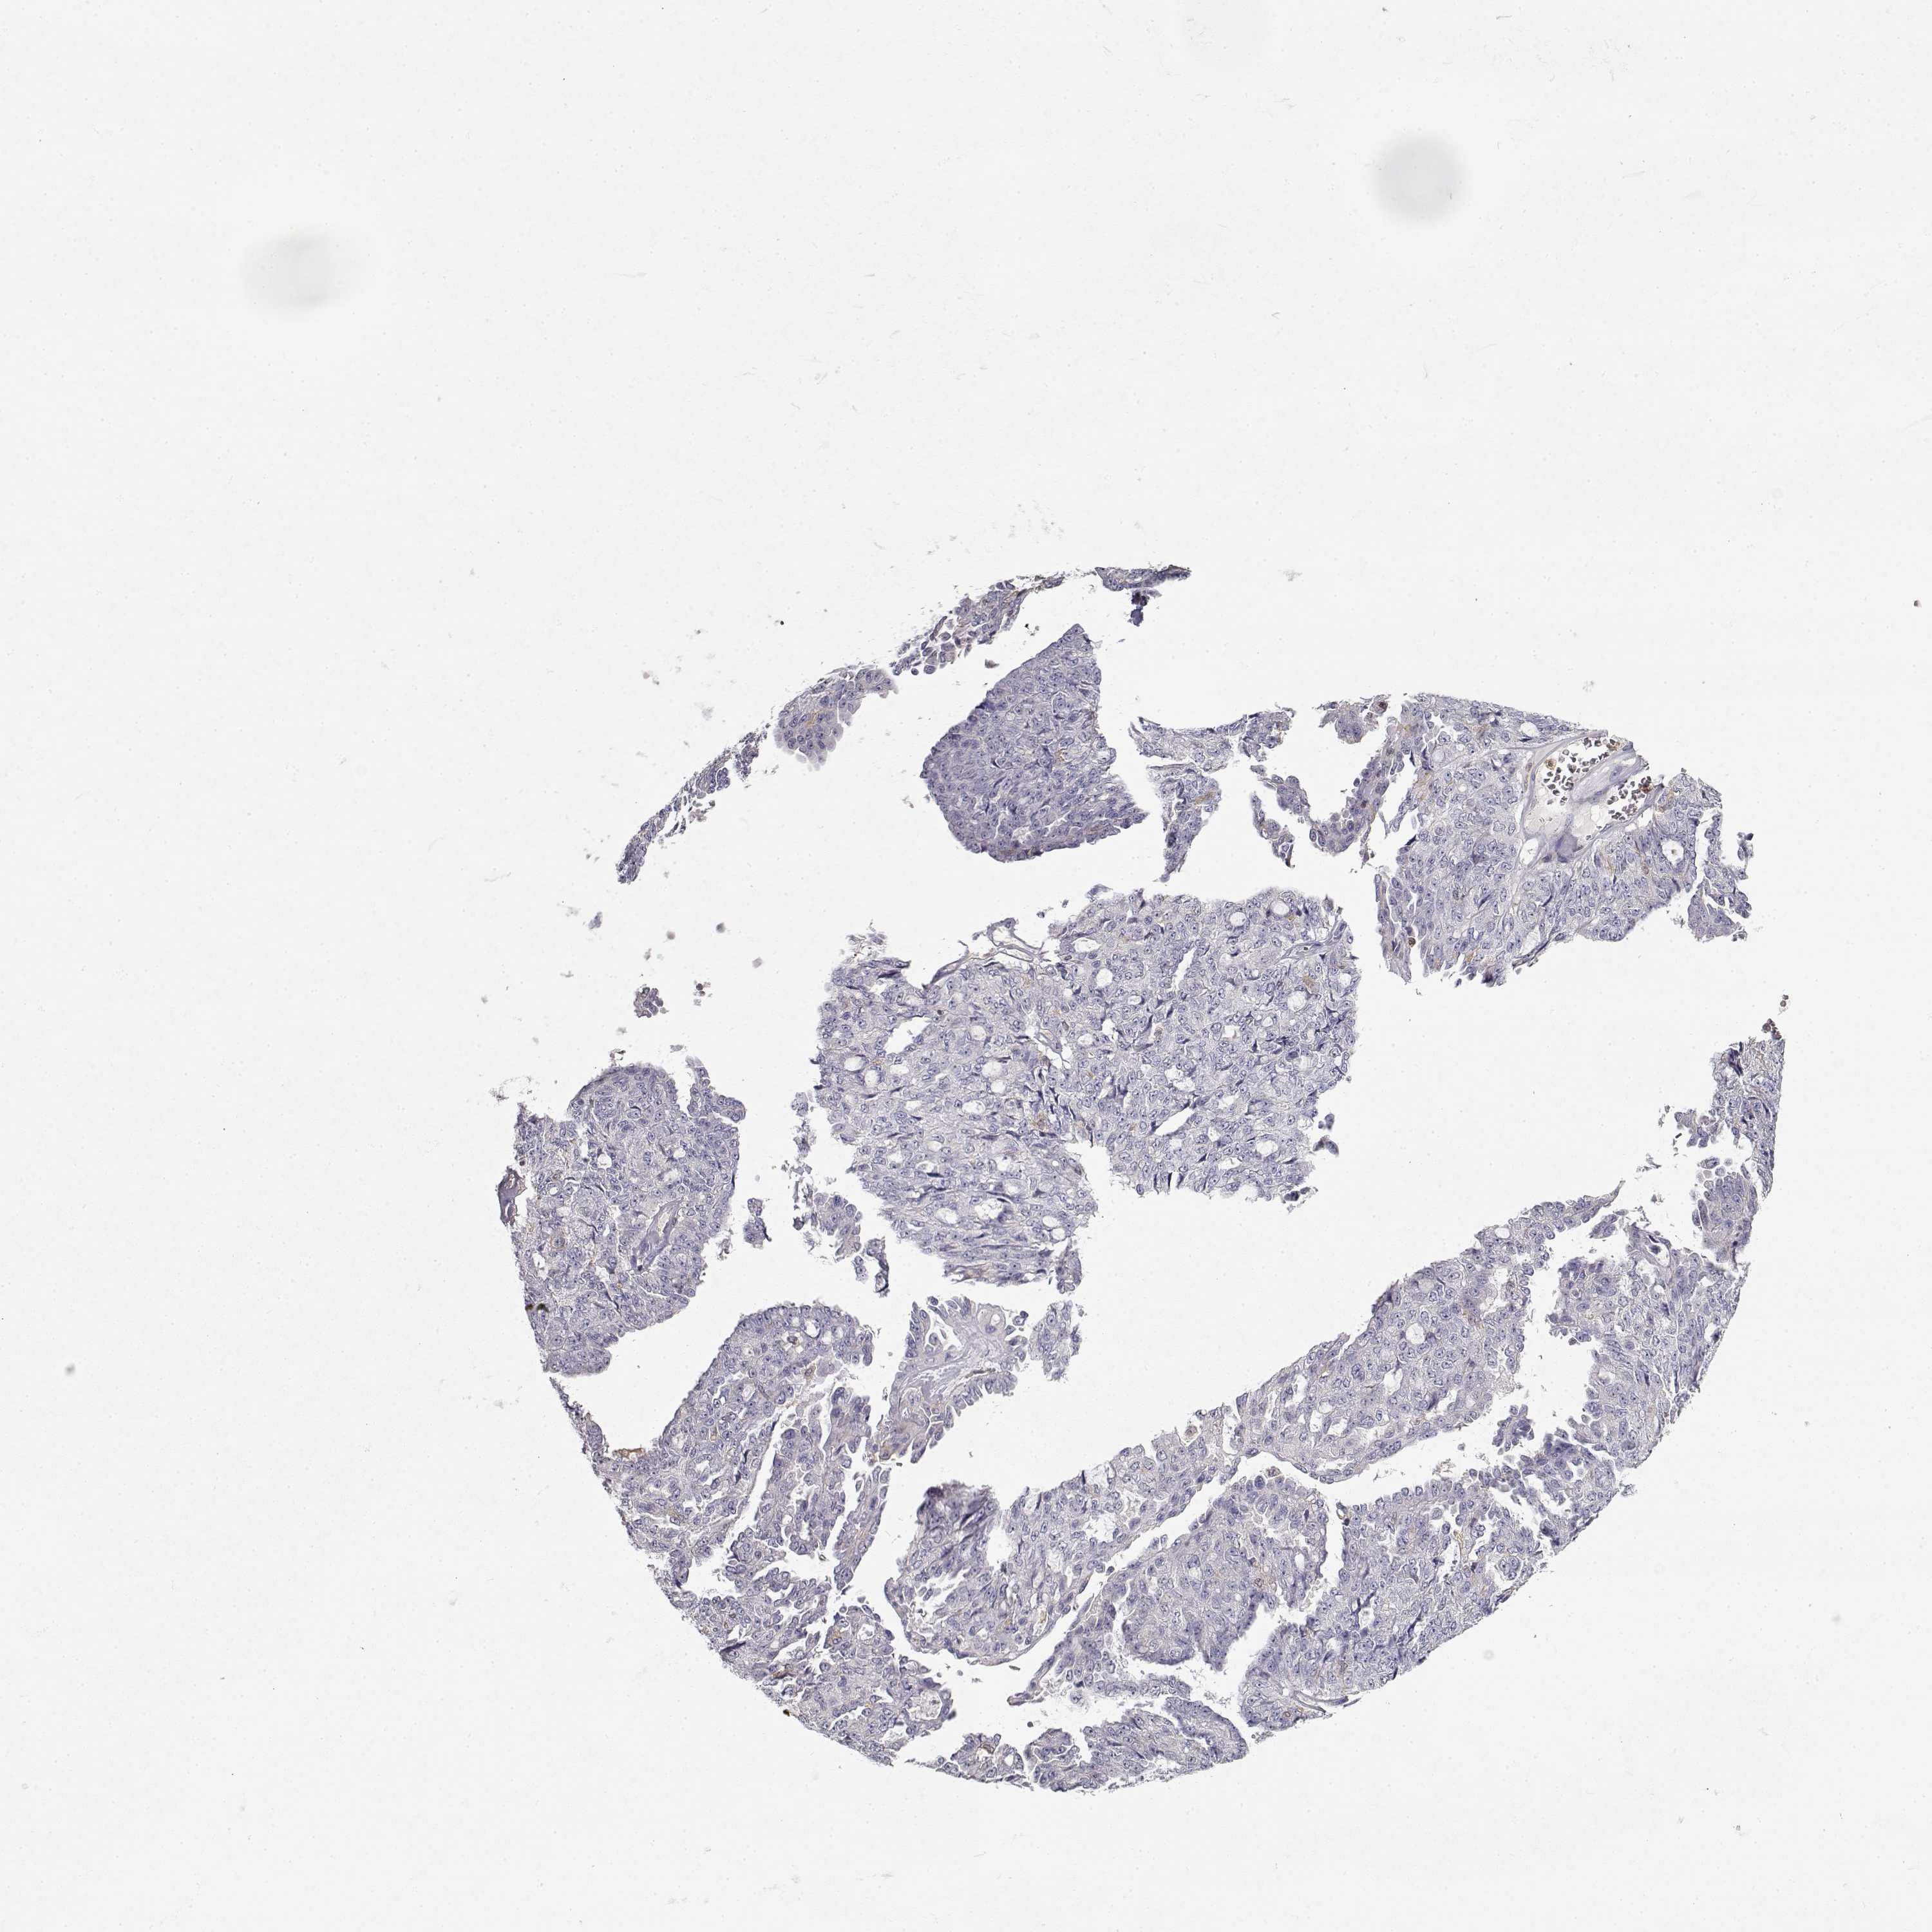

OVARIAN CANCER - Protein expressioni

A mouse-over function shows sample information and annotation data. Click on an image to view it in a full screen mode. Samples can be filtered based on level of antibody staining by selecting one or several of the following categories: high, medium, low and not detected. The assay and annotation is described here.

Note that samples used for immunohistochemistry by the Human Protein Atlas do not correspond to samples in the TCGA dataset.

Antibody stainingi

Antibody staining in the annotated cell types in the current human tissue is reported as not detected, low, medium, or high, based on conventional immunohistochemistry profiling in selected tissues. This score is based on the combination of the staining intensity and fraction of stained cells.

Each image is clickable and will lead to virtual microscopy that enables deeper exploration of all samples and also displays staining intensity scores, fraction scores and subcellular localization as well as patient and tissue information for each sample.

Antibody HPA001864

Staining

High

Medium

Low

Not detected

Intensity

Strong

Moderate

Weak

Negative

Quantity

>75%

75%-25%

<25%

None

Location

Nuclear

Cytoplasmic/membranous

Cytoplasmic/membranous,nuclear

Cystadenocarcinoma, serous, NOS

Cystadenocarcinoma, mucinous, NOS

Carcinoma, endometroid